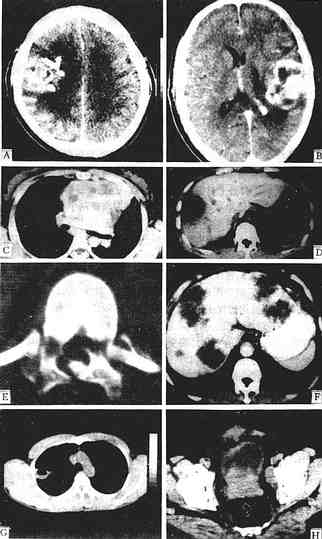

CT诊断应用于各系统疾病有以下特点及优势,参考图1-2-6。

图1-2-6 CT图像

少支胶质细胞瘤增强,右额、顶叶有一较大不规则肿块,强化不均,周围有低密度水肿区

星形细胞瘤 增强,左额顶叶有一不均匀强化肿块,不规则,内有未有强化的低密度区,周围有低密度水肿区,中线结构右移

胸腺增生 平扫,胸腺区有一分叶状密度均一病灶,仍呈胸腺状,主动脉受压右移

肝脓肿 平扫,肝右叶有一低密度灶类圆形,中心部密度更低为脓腔,周边为脓肿壁呈“双边征”

腰椎骨折 平扫,椎弓多处中断,椎管变形,其内可见碎骨片

肝转移癌 增强,肝左、右叶多个大小不一、不规则低密度灶,周边有细的强化环围绕

肺脓肿 平扫,右上叶有一空洞性病灶,内壁光滑,并见气液平面,胸部X线片曾疑肺癌

前裂腺癌 平扫,前列腺分叶状增大,并向膀胱内突入